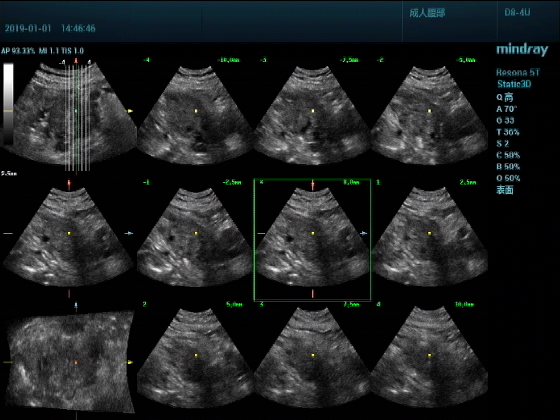

超声入门贴959--胰头癌并胰管扩张

男,88岁,腹部隐疼2个月加重3天来诊